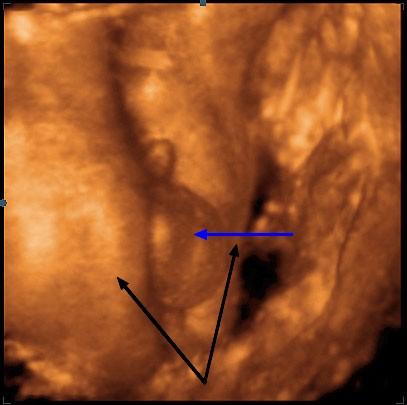

Detail zadečku miminka ve 30. týdnu těhotenství. Plod je mužského pohlaví. Mezi stehny plodu (černé šipky) je zřetelný penis, pod ním šourek (modrá šipka).